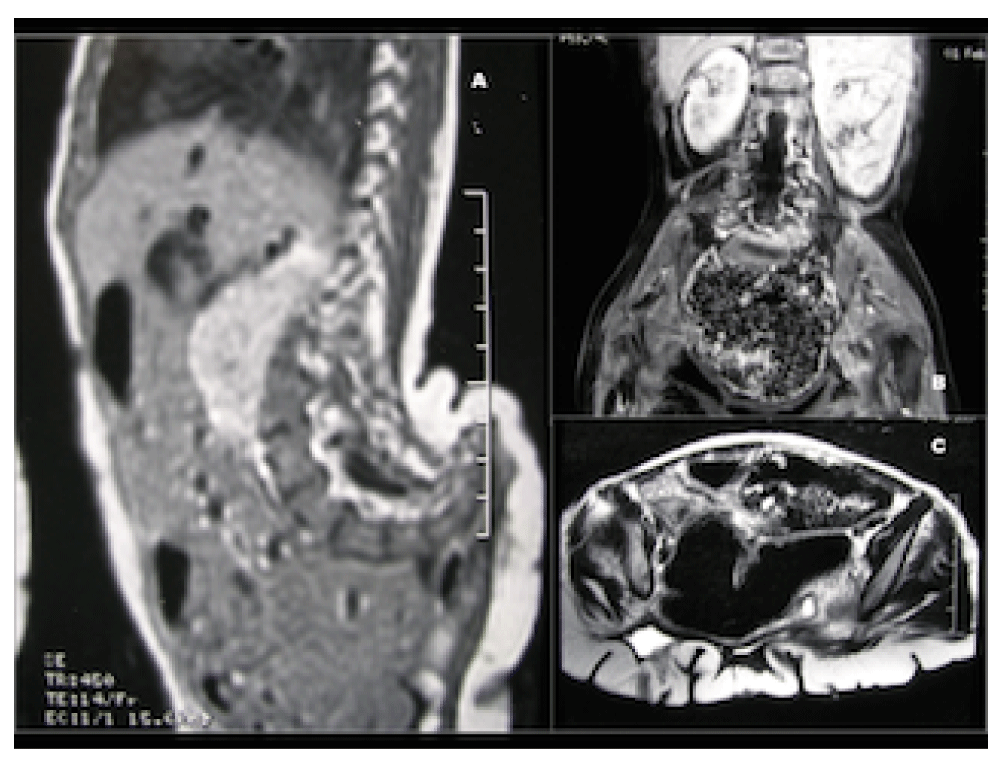

Laboratory examination showed a normal blood count and renal function, and the karyotype was 46, XY. Pelvic radiographs demonstrated an exaggerated sacrococcygeal concavity, lumbar dysrrhaphism and pubic dyastasis. The dorsal bony prominence corresponded to the sacrococcygeal spine, whose abnormal concavity oriented its tip upward, like a small tail. The contrast injection through the orifice of the mass showed a large cavity that extended sagittally and laterally. MRI confirmed the previous findings and revealed a right crossed ectopic kidney, intestinal malrotation, a hypoplastic infrarenal inferior vena cava and a hypoplastic right iliac artery. The posterior concavity of sacrococcygeal bones, associated to a deformity of the pelvic rim was evident, as well as the cavity below the convoluted skin and subcutaneous layer of the perineal mass (Figure 3). The endoscopic evaluation through the orifice revealed a cavity lined by urothelial mucosa, with a small communication to the anterior urethra in its anterior wall. The ureteral orifices were not identified, although urine accumulated in the cavity during the examination.

Nuclear magnetic resonance demonstrating exaggerated sacrococcygeal convexity (A); crossing ectopic right kidney and an intestinal malrotation (B); absence of pubic bone, and the corrugated skin covering the posterior perineal cavity (C).